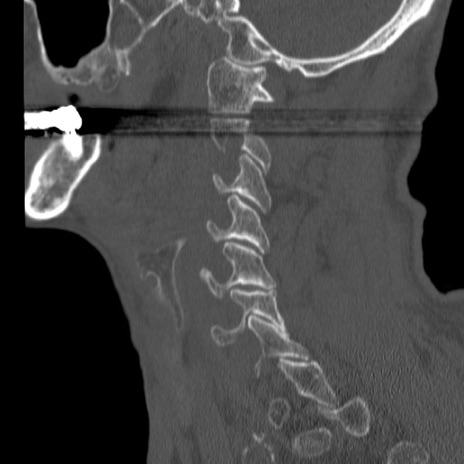

症例46 頚椎CT(矢状断像)

【症例】80歳代男性

【主訴】両側頚部〜上肢のしびれ

【現病歴】昨日、自宅内で転倒、その後より上記症状あり。意識障害なし。

【身体所見】両側上肢のallodynia(熱痛覚過敏)あり。MMTおよびDTRは正確な所見取れず。両上肢の挙上はなんとか可能。

異常所見と診断は?